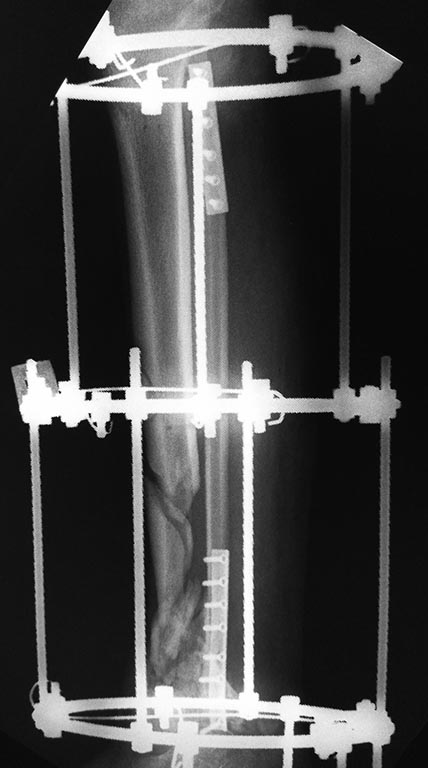

Добрый вечер, уважаемые коллеги.  Представляю Вам пациента после,

кататравмы ,  которая случилась в декабре 2016г. Длительное время

лечился в стационаре, множество повреждений поэтапно было оперировано.

Что касаемо голени, перелом был закрытый.

Выполнена открытая адаптация отломков б/берцовой кости, комбинированный

остеосинтез костей голени. Рана зажила первично. В настоящее время

пациент передвигается самостоятельно при помощи костылей и из всех

повреждений, вопрос с голенью остался не решенный. Представляю вам

снимки первичные при поступлении и голень в аппарате на сегодняшний день.